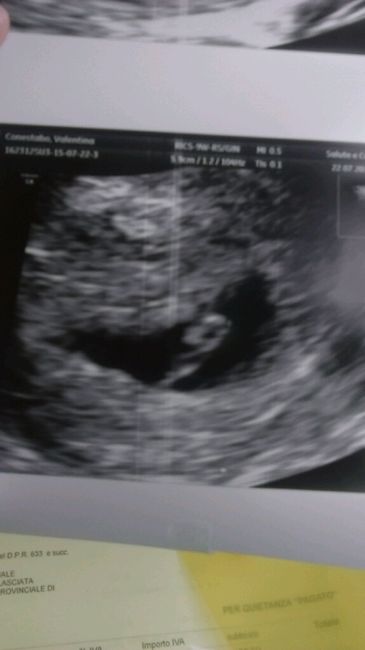

Eccolo...finalmente la prima eco

Da Valentina , Il 22 Luglio 2015 alle 19:15

Ciao mamme...volevo condividere con voi la prima ecografia...ecco a voi il mio/mia fagiolino/a....la data presunta sarà il 13 marzo..abbiamo anche visto il cuoricino...